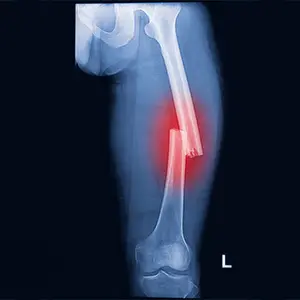

• Orthopaedic reconstruction: Once the patient is stable, orthopaedic injuries are addressed. This can include external or internal fixation of fractures, joint realignment, soft-tissue reconstruction and staged surgeries for open or contaminated wounds. Early fixation where appropriate helps reduce complications and facilitates rehabilitation.

Pelvic fractures with associated organ injury, multiple long-bone fractures, open fractures with severe soft-tissue loss, and distal tibial (Pilon) fractures are typical examples.